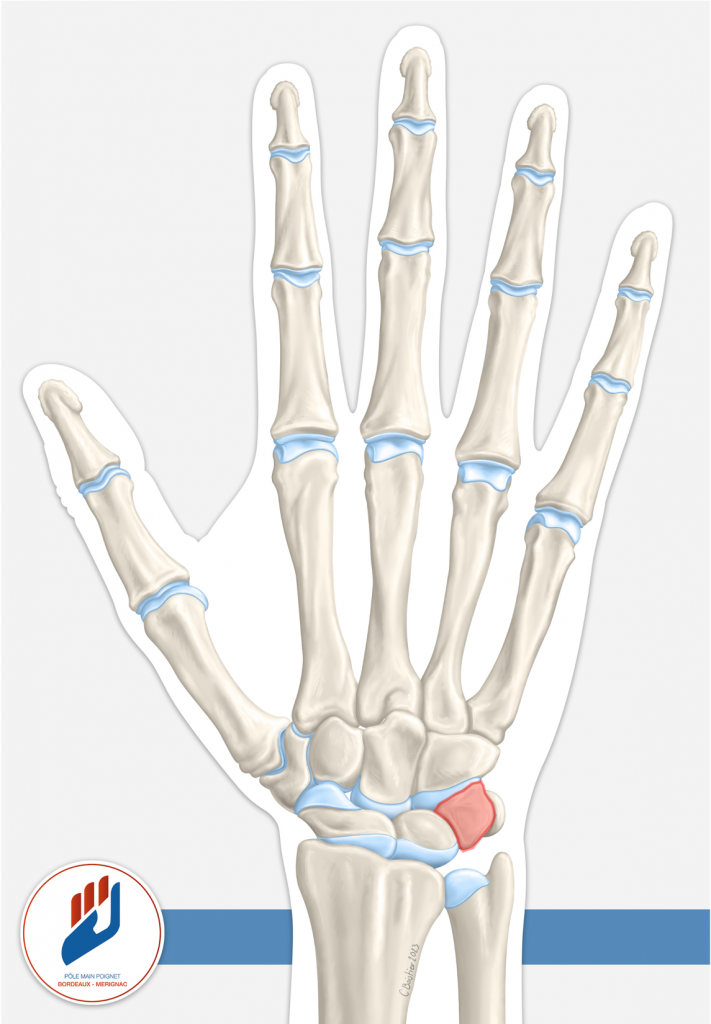

Le triquétrum est l’un des huit petits os qui composent le carpe (le « poignet osseux »). Il est situé du côté ulnaire du poignet (côté du petit doigt) et constitue le deuxième os carpien le plus souvent fracturé, après le scaphoïde. Bien que ces fractures soient moins connues que celles du scaphoïde, elles méritent une attention particulière pour éviter toute complication et assurer une bonne récupération.

Souvent, la fracture du triquétrum se présente sous forme d’une « fracture-chip » (un petit fragment osseux détaché) sur la face dorsale de l’os au point d’insertion du ligament radiocarpien dorsal (cf schéma). D’autres formes plus complexes (fracture du « corps » du triquétrum ou fracture sur la face palmaire) peuvent aussi exister, notamment dans des traumatismes plus sévères.